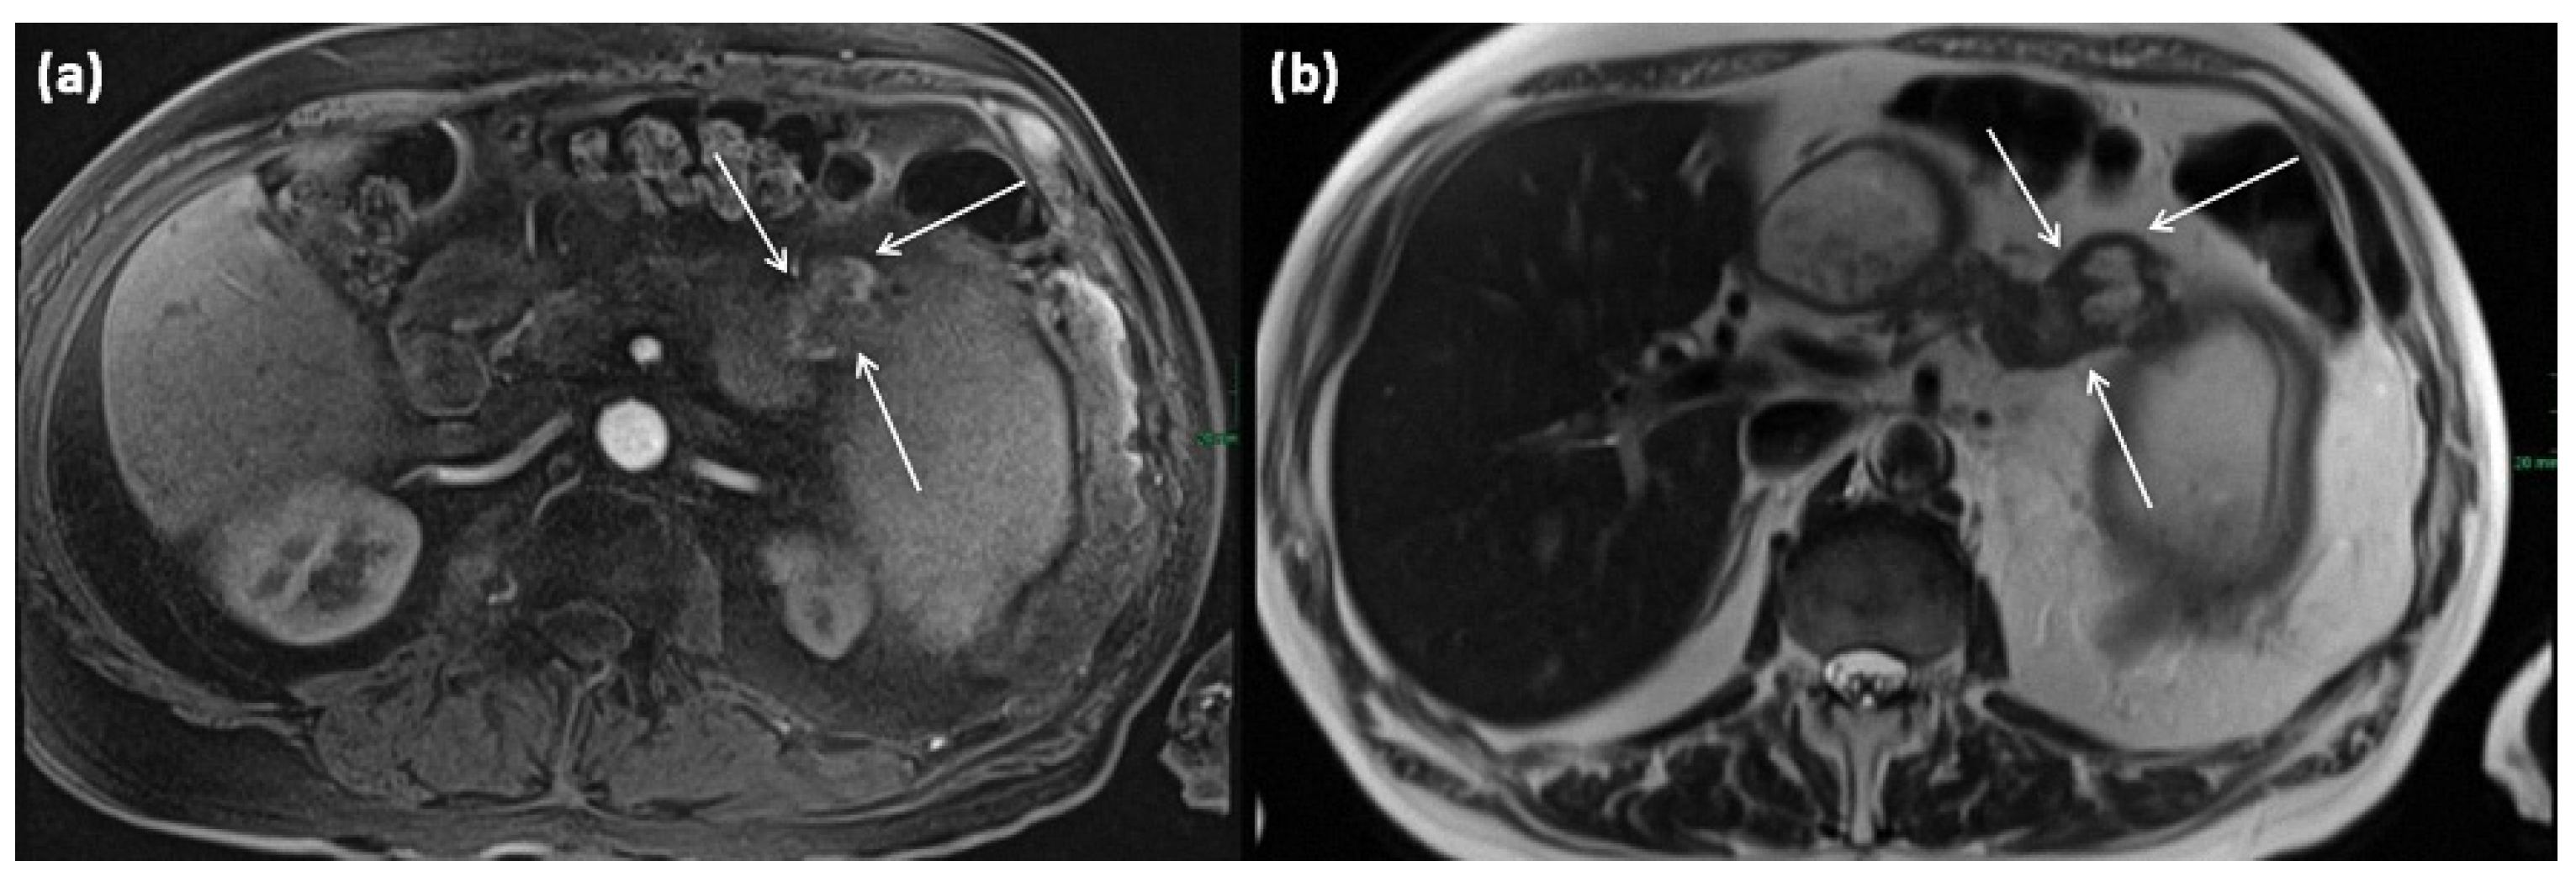

Another rare subtype is cystic lymphangioma of the pancreas, which is considered a congenital malformation of the lymphatic system []. It results in the formation of multilocular cystic lesions, which are considered indolent and are usually discovered incidentally. A clustered occurrence in women has been described []. Some of these can reach enormous sizes of more than 10 cm and can also be palpable as a mass. On imaging, they are sharply delineated multilocular lesions, often with KM enhancement of the capsule or thin internal septa (Figure 19). Rarely, phlebolithic calcifications may be present. On MRI, cyst spaces appear hypointense on T1-weighted images and hyperintense on T2-weighted images []. Any fine-needle aspiration shows nonspecific features (Figure 20) [].

Figure 19.

MRI of a 79-year-old female patient with axial T1w (a) after gadolinium-based contrast administration, T2w, and (b) magnetic resonance cholangiopancreaticography (MRCP) (c). A merging and communicating multicystic formation is seen at the head of the pancreas, with the single cystic parts showing marked differences in size. Septa show mild contrast enhancement. In T2w a homogenous hyperintense signal is present. The tumor is marked with arrows in all sequences.